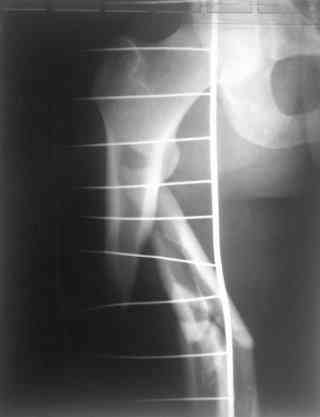

Re: С3-перелом бедра как лечить дальше?....

Надеюсь сейчас показать перелом, а потом синтез.